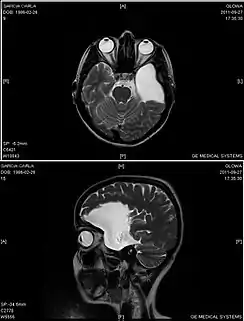

Resonancia magnética de una paciente de 25 años con un quiste aracnoideo frontotemporal izquierdo.

El diagnóstico se realiza principalmente por resonancia magnética. Frecuentemente los quistes se hallan incidentalmente en resonancias magnéticas realizadas por otras razones clínicas. En la práctica, el diagnóstico de quistes aracnoideos sintomáticos requiere la presencia de los síntomas; en muchos casos esto nunca ocurre.